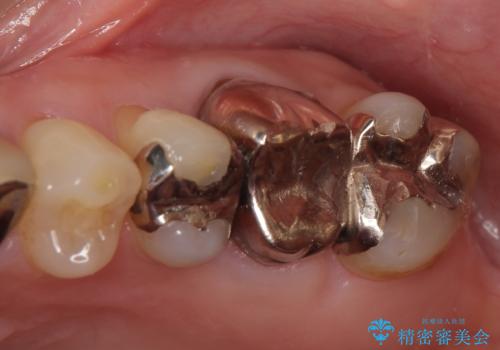

- 左上6番目の歯が疼くので診て欲しいといらっしゃった方の症例です。

左上6のクラウン及びコアを除去したところ、歯根が破折していたため抜歯し、ブリッジによる補綴を行いました。